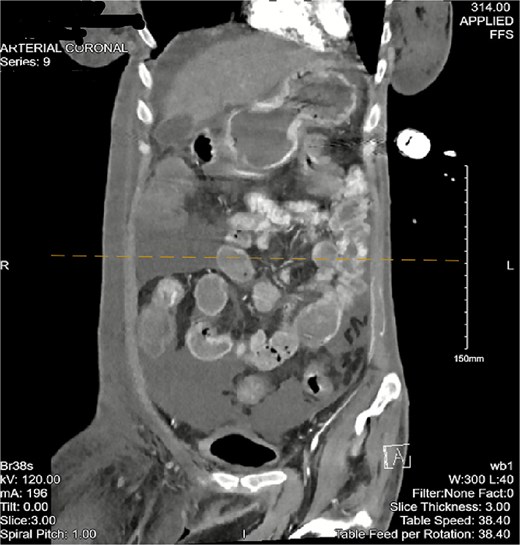

Computed tomography (CT) angiogram of the chest demonstrated numerous small nodular and patchy opacities throughout the upper lobes ranging from punctate to 1.2 cm in diameter (Figs 1 and 2). Additionally, bilateral pleural effusions with extensive atelectasis were also observed.

The patient then began having continuous bloody bowel movements with requirements for multiple blood transfusions. CT angiogram of the abdomen and pelvis demonstrated wall thickening of the cecum/ascending colon and distal active extravasation of contrast (Figs 3 and 4). These findings were consistent with a cecal mass. A massive transfusion protocol was initiated and interventional radiology was emergently consulted for angioembolization.

CT angiogram of the abdomen and pelvis—arterial phase with a coronal cross section. Patchy contrast extravasation is observed in the ileocecal region with adjacent distal wall-thickening. Distended loops of small bowel with mesenteric fat stranding are observed. Significant abdominopelvic free fluid is seen, correlating with ascites. Enlarged mesenteric lymph nodes are observed.

CT of the abdomen and pelvis with a coronal cross-section. Asymmetric wall thickening is observed in the cecum and ascending colon with adjacent fat stranding. Proximal dilation of small bowel loops with mesenteric stranding is also seen. Significant abdominopelvic free fluid is demonstrated. The CT findings correlate with mass versus inflammatory colitis. The read was addended to reflect concerns for cecal mass.